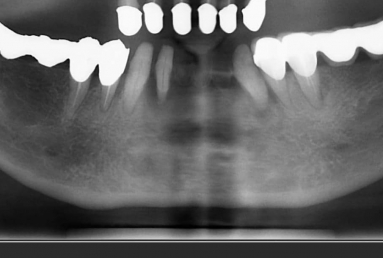

Female patient with advanced periodontal disease has mobility of all teeth and old dental work. All mandibular teeth were extracted and replaced with 4 dental implants ( Alpha bio Nobel).